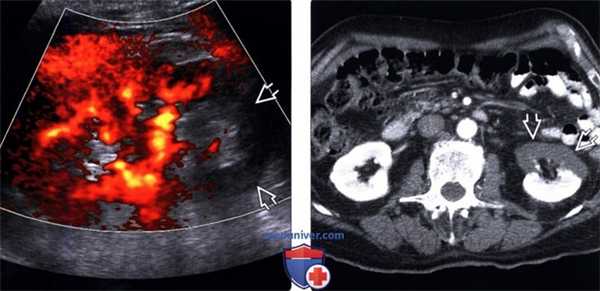

(Левый) При цветовой допплерографии визуализация кровотока в нижнем полюсе почки у пациента с инфарктом почки на фоне фибрилляции предсердий отсутствует. Наиболее чувствительным методом выявления медленных токов является энергетическая допплерография, которая должна использоваться для подтверждения диагноза инфаркта.

(Правый) При КТ с контрастированием у того же пациента визуализируется отсутствие перфузии в переднем отделе коркового вещества почки.